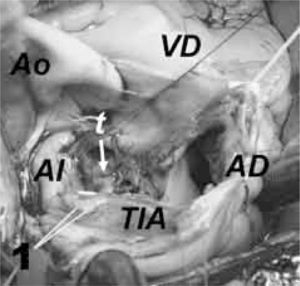

Se inicia la sección con tijera de todo el espesor del septo interauricular donde se unen los techos de ambas aurículas, entre la vena cava superior y aorta ascendente, abarcando el área donde asienta la base de implantación tumoral, con un margen de seguridad peritumoral de 2–3mm. La pinza de disección sólo se utiliza para separar cuidadosamente el cuerpo tumoral de su base de implantación, pero nunca se presiona entre las ramas de la pinza el mixoma (Fig. 2).

Teniendo en consideración estos detalles técnicos, es decir, iniciar la resección desde la porción más superior del septo y avanzar hacia la parte más inferior, ayudándose de un aspirador no rígido en aurícula izquierda, y con las pinzas de disección a modo de separador romo, hemos conseguido extirpar con facilidad, en una sola pieza y sin fragmentación, tres mixomas de aurícula izquierda de gran tamaño (Fig. 3).